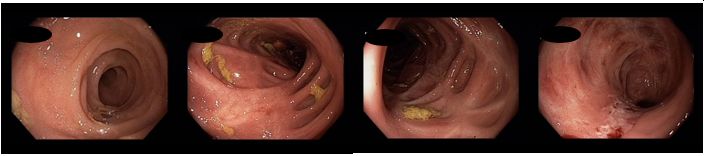

Koloskopie 2013/7: Endoskopický obraz těžké, segmentální pankolitidy. Plazivé ulcerace rekta, sigmoidea a descendens. Drobné afty c. transversum a céka. Normální nález v terminálním ileu

Koloskopie 2014: Endoskopický obraz mírné segmentální pankolitidy (aftózní léze, nálety fibrinu, reziduální drobné ulcerace po původně serpiginózních vředech). Nápadné pozánětlivé změny (jizvy, polypy), retrakce zejména v levém tračníku. Normální terminální ileum

Koloskopie 2017/2: Aktivní zánětlivé změny (serpiginózní ulcerace) v oblasti rektosigmatu, mírné zánětlivé změny v blízkosti hepatálního ohbí, segmentálně pozánětlivé změny zejména v levém tračníku (jizvy, retrakce). Normální terminální ileum

Koloskopie 2018/8: Mírné floridní zánětlivé změny (ložiskové zarudnutí a setřelá podslizniční cévní kresba, aftoidní léze) v blízkosti hepatálního ohbí v colon ascendens a v sigmatu. Pozánětlivé změny (jizvy po serpiginózních ulcerací v příčném a levém tračníku, vlevo i pozánětlivá trabekulizace. Normální terminální ileum.

Koloskopie 2022/2: Pozánětlivé změny celého tračníku (jizvy), v rektosigmatu je reziduální ulcerace v centru serpiginózní ulcerace – bez makroskopických známek aktivity v tračníku i terminálním ileu. Vyšetření v bílém světle i NBI